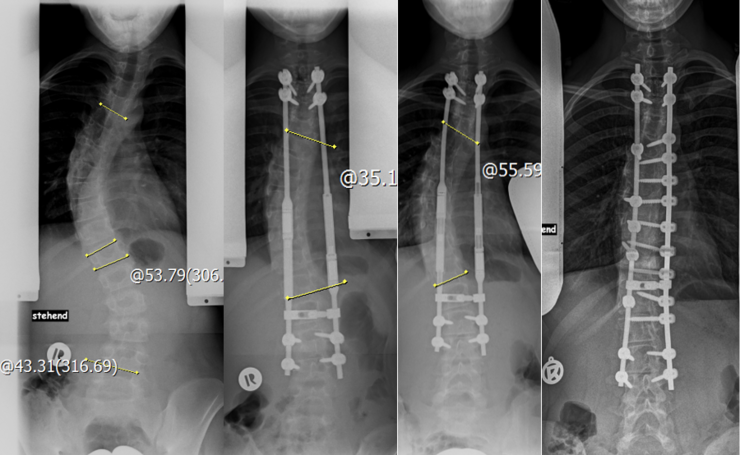

Magec rods: Beispielverlauf mit Wachstumsstäben

Der Wachstumsstab dient also vor allem dazu, die Zeit bis zur endgültigen Skoliose-Operation zu überbrücken, wenn eine Korsettversorgung nicht ausreichend ist. Auch wenn der Knochen noch nicht fusioniert (versteift) wird, ist man damit nicht beweglicher. In dem Bereich, in dem der Stab angebracht ist, ist die Wirbelsäule komplett unbeweglich. Die OP-Strecke ist in der Regel länger als bei den modernen Fusionsverfahren und da immer die Gefahr der Stablockerung oder des Stab-Bruchs besteht, ist man sportlich sehr eingeschränkt. Manchmal kommt es sogar zu einer spontanen Fusion der Wirbelsegmente allein durch die Ruhigstellung. Daher wird diese OP-Methode nur empfohlen, wenn eine Korsettbehandlung nicht möglich und die Patientinnen und Patienten für die endgültige OP noch deutlich zu jung sind. Für viele sehr junge Patientinnen und Patienten sind die Magnetstäbe die einzige Möglichkeit.